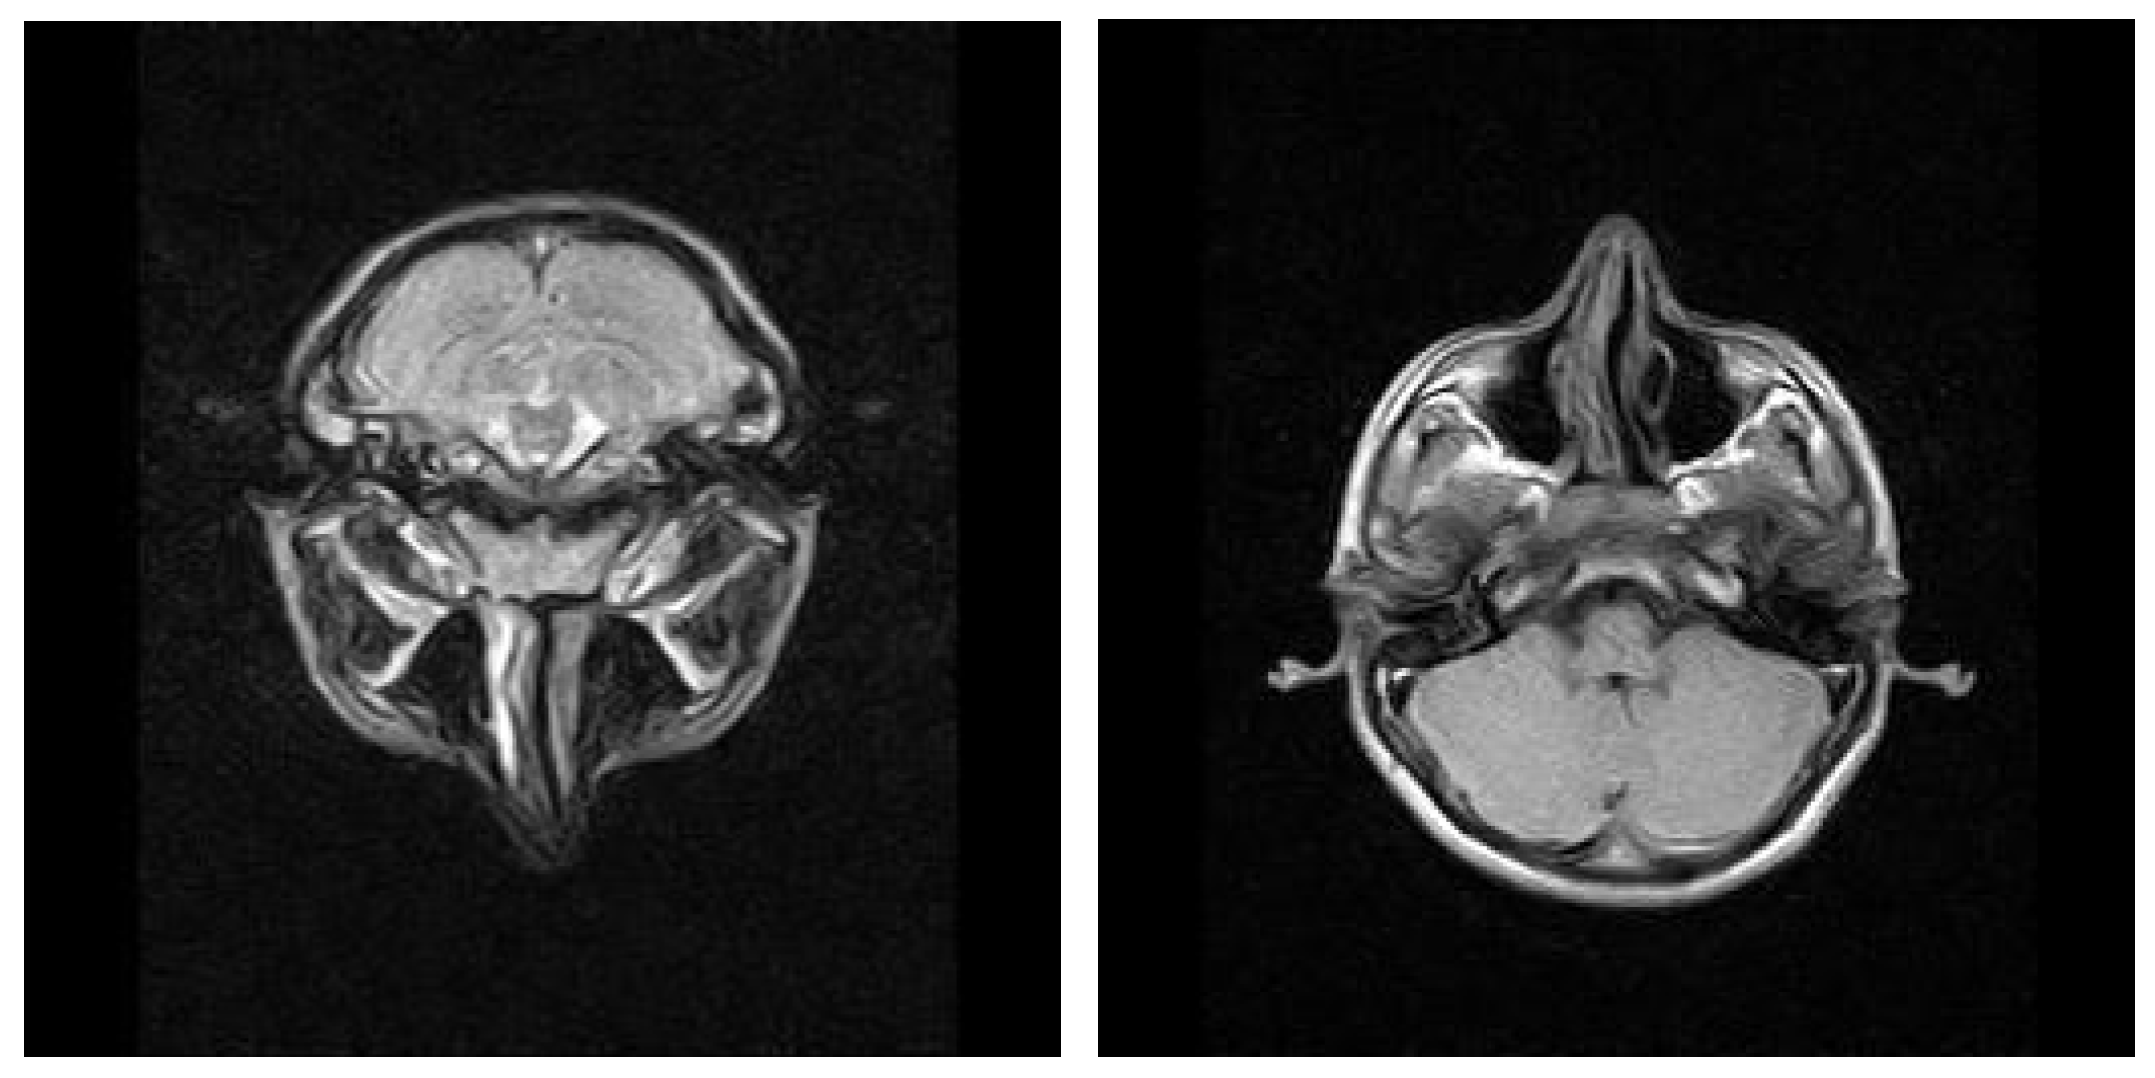

3.1.2. Computed Tomography and Magnetic Resonance Imaging

| MRI Aspects | Number of Patients | Percentage |

|---|---|---|

| Edema | 128 | 100% |

| Cholesteatoma | 40 | 31.25% |

| Exocranial extensions | 40 | 31.25% |

| Intracranial extensions | 32 | 25% |

| Inner ear damage | 20 | 15.62% |